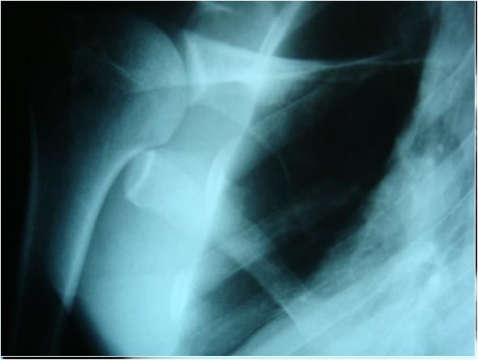

- RX: fratura da escápula

- Tto: Tipóia e Sintomáticos